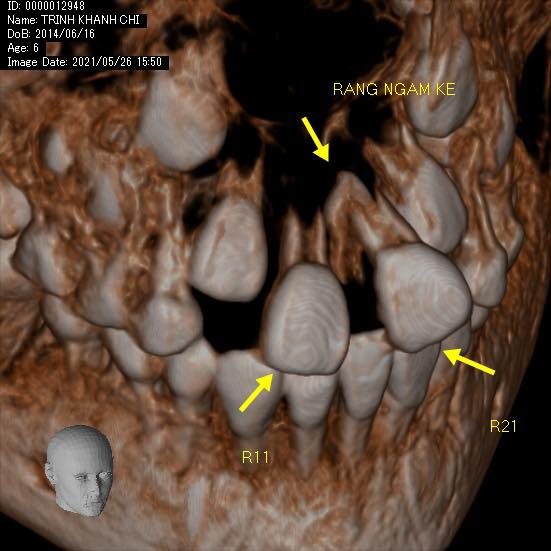

#khớpcắnhở #openbite Dr. Thy Nga Nguyen